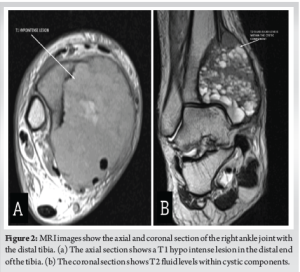

A 36-year-old male presented after noticing a gradually increasing swelling over his right ankle for the past 3 months. It was associated with a dull and diffuse type of pain which was aggravated with weight bearing. He denied a history of any previous trauma. He had noticed significant weight loss in the past 6 months. On clinical examination, there was a localized swelling of size 5 × 3 cm over the medial aspect of the ankle, which was tender, immobile, with ill-defined edges, and was bony hard in consistency. The range of movements in the ankle was minimally restricted in comparison with the contralateral side. There was no neurovascular deficit in the affected limb. Plain radiographs of the affected limb were done and showed an ill-defined, radiolucent, expansile lesion in the medial aspect of the distal end of the tibia, with a posteromedial cortical breach and a narrow zone of transition (Fig. 1a and b). Magnetic resonance imaging of the affected limb was performed and showed a T1 hypointense lesion of size 6.1 × 4.7 × 7.3 cm in the epi-metaphyseal region of the distal tibia (Fig. 2a), with multiple cystic areas and fluid levels (Fig. 2b) – suggestive of giant cell tumor of the distal tibia with secondary aneurysmal bone cyst formation. Biopsy was performed from the lesion, under ultrasound guidance, and showed osteoclast-like giant cells and neoplastic cells with ill-defined borders and eosinophilic cytoplasm, suggestive of giant cell tumor. Based on the radiographic appearance, the tumor was classified according to the Campanacci grading as Type III owing to the presence of ill-defined margins and a cortical breakthrough. After a thorough review of the literature and a multidisciplinary discussion with the surgical oncology team in assessing all the possible options of intervention, pre-operative planning was done, and the patient underwent wide excision of the tumor and was planned for bone transport with an Ilizarov ring fixator (Fig. 3a and b). The patient was positioned supine on the operating table with a primary surgeon on the right side and an image intensifier on the contralateral side. The skin incision was made over the posteromedial aspect, extending from the distal third of the leg to mid-foot (Fig. 4a). The flap was raised posteriorly (Fig. 4b), posterior compartment was dissected, and the great saphenous vein was isolated along its course. Tumor margins were identified, and tibia was osteotomized, giving a 3 cm clearance proximal to the tumor (Fig. 4c). Ligaments around the ankle were cut, and the distal end of the tumor was visualized. The tumor, along with the encased tibialis posterior, was removed in toto (Fig. 4d) and was sent for histopathological examination. A thorough wash was given, and the wound was closed. Three equidistant Ilizarov rings were fixed around the tibia proximal to the osteotomy site using tensioned wires and were interconnected with threaded rods. A half ring was fixed around the midfoot with tensioned wires and connected to the proximal rings (Fig. 5). Proximal tibial corticotomy was done at a level between the proximal and middle rings. Postoperatively, distraction was started from day 7, at the rate of 1mm/day, and was continued for a period of 90 days, resulting in a distraction of 90 mm at the corticotomy site, thereby filling the defect in the distal tibia. Serial radiographs were done to look for consolidation of the regenerate at distraction site and docking of the stump over the talus (Fig. 6a-c). 90 days later, once docking was complete (Fig. 6d), distraction was stopped, and the frame was retained for a period of 180 days, allowing for consolidation of regenerate at the distraction site. Once clinical and radiological signs of union were confirmed at the distraction site, acute docking was performed, and fusion at the ankle was done. The Ilizarov frame was then retained for a period of 6 months. After 6 months, once complete union was noticed at the docking site, the frame was (Fig. 6e and f). The patient was then gradually made to weight bear partially with a walker frame for a period of 4 weeks. Later he was allowed full weight-bearing walking, initially with a walker frame for 2 weeks, followed by an elbow crutch for 2 weeks and unassisted subsequently. He was last followed up 2½ years postoperatively and showed no clinical or radiological signs of recurrence. He was able to walk unassisted with a plantigrade foot. Dorsiflexion and plantarflexion at the ankle were not possible. Minimal passive inversion and eversion movements at the subtalar joint were preserved.